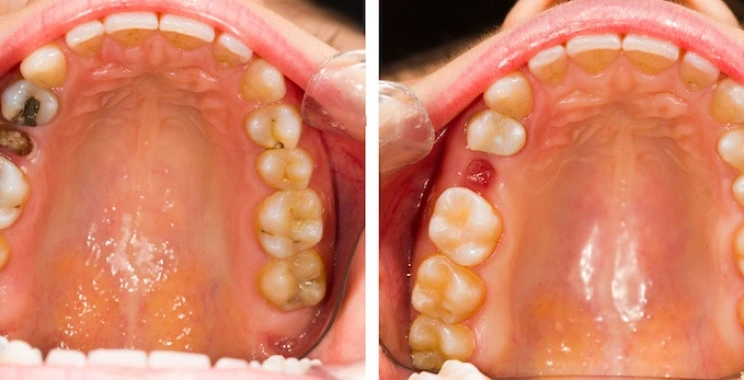

علاج الضرس المحفور الملتهب

علاج الضرس المحفور الملتهب يعتمد على شدة الالتهاب ومرحلة التسوس. في الحالات البسيطة، يبدأ العلاج بتنظيف التسوس جيداً ثم حشو الضرس لحمايته ومنع تفاقم المشكلة. إذا وصل الالتهاب إلى عصب الضرس، يجب إجراء علاج العصب عبر سحب العصب وتنظيف قنوات الجذر ثم حشوها، مما يخفف الألم ويمنع انتشار الالتهاب. بالإضافة للعلاج الطبي، يمكن تخفيف الألم مؤقتًا باستخدام مضادات الالتهاب والمسكنات التي يصفها الطبيب، وتطبيق كمادات باردة على الخد لتقليل التورم، وكذلك المضمضة بالماء الدافئ مع الملح أو استخدام زيت القرنفل كمسكن طبيعي. في الحالات المتقدمة جداً التي لا يمكن فيها إنقاذ الضرس.

قد يلجأ الطبيب إلى خلع الضرس من المهم زيارة طبيب الأسنان لتقييم الحالة بدقة والحصول على العلاج المناسب لمنع المضاعفات

علاج العصب ( الحشو العلاجي )

في حالة كان الالتهاب وصل للعصب يتم عمل حشو عصب الاسنان للمريض باستخدام تقنيات دقيقة تتوفر داخل مجمع الطب المتميز بالمدينة المنورة. حيث يقوم الطبيب بتنظيف القنوات الداخلية للضرس وإعادة حشوها بمادة طبية تمنع رجوع العدوى مرة أخرى للضرس.

فتح و تصريف الخراج

في حالة تكون خراج داخل الضرس واللثة يقوم الطبيب بفتحه وتصريف الصديد مع إعطاء المريض العلاج المناسب. مما يساعد على تخفيف التورم بشكل سريع.